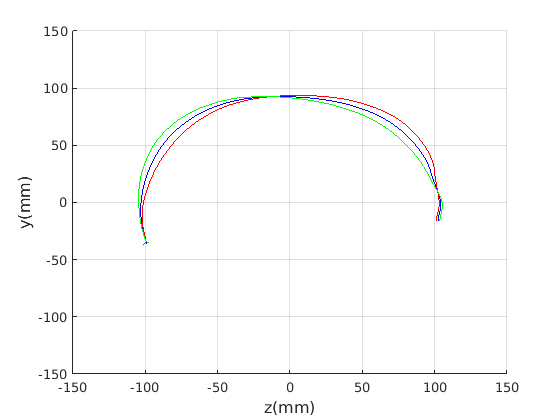

8 A case study of cranial profile model use for intervention outcome evaluation

In this section we take a sample of 25 boys, who are craniofacial craniosynostosis patients, 14 of which have undergone one type of corrective procedure (BS) and the other 11, another corrective procedure (TCR). Providing that the heads are sufficiently symmetrical and are amenable to ellipse fitting, we can parameterise all of these patients’ heads using our scale-normalised craniofacial profile model (2D model with face cropped out). We can then plot their pre-operative and post-operative parametrisations and compare them with the parameterisations of the 100 training examples. The expected result is that the parameterisations should show the head shapes moving nearer to the mean of the training examples. It also reveals which of the dominant modes of shape variation are most affected. The results are shown in figures 31 and 32.

For the BS patient set, the Mahalanobis distance of the mean pre-op parameters (red triangle in Fig. 31) is 4.670, and for the mean post-op parameters (blue triangle) is 2.302. For shape parameter 2 only these figures are 4.400 and 2.156.

For the TCR patient set, the Mahalanobis distance of the mean pre-op parameters (red triangle in Fig. 32) is 4.647, and for the mean post-op parameters (blue triangle) is 2.439. For shape parameter 2 only these figures are 4.354 and 2.439. We note that most of this change occurs in parameter 2, which corresponds to moving height in the cranium from the frontal part of the profile to the rear. In these figures we excluded one patient, who preoperatively already had a near-mean head shape (see red cross near to the origin in Fig. 32, so any operation is unlikely to improve on this (but intervention is required in order to relieve potentially damaging inter-cranial pressure).

It is not possible to make definitive statements relating to one method of intervention compared to another with these relatively small numbers of patients. However, the cranial profile model does show that both procedures on average, lead to a movement of head shape towards the mean of the training population. An example of analysis of intervention outcome for a BS patient is given in Fig. 33 and a TCR patient is given in Fig. 34. The particular example used is highlighted with circles on figures 31 and 32 to indicate pre-op and post-op parametrisations. To our knowledge this is the first use of statistical 3D craniofacial shape models in a clinical study.